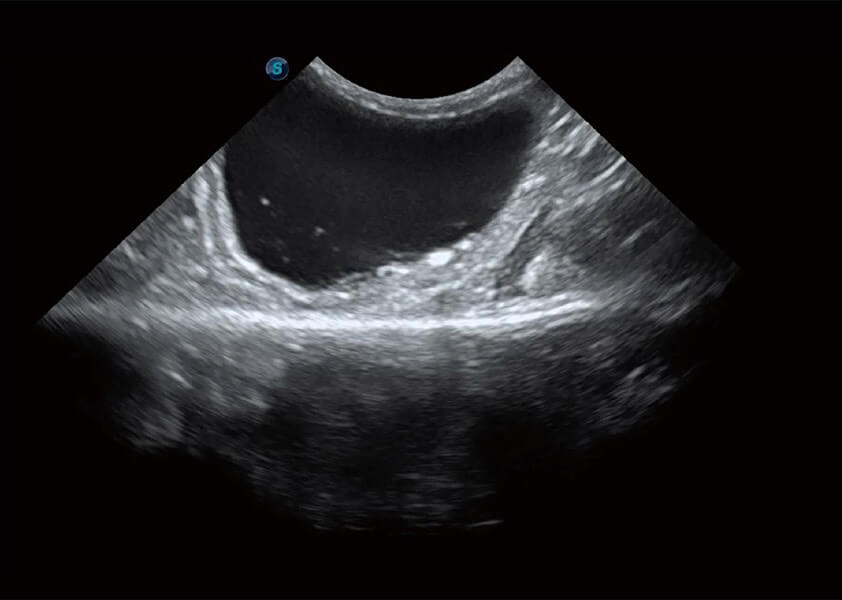

(犬)胆囊泥沙

(猫)膀胱结晶